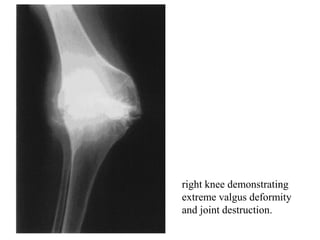

Roentgonograms

• In advance stage,

– gross destruction and deformation of bone ends,

– osteolytic cavities,

– tubercular sequestra and

– triple deformity may be seen

right knee demonstrating

extreme valgus deformity

and joint destruction.